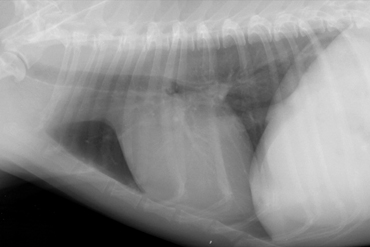

Normal cardiac structures.